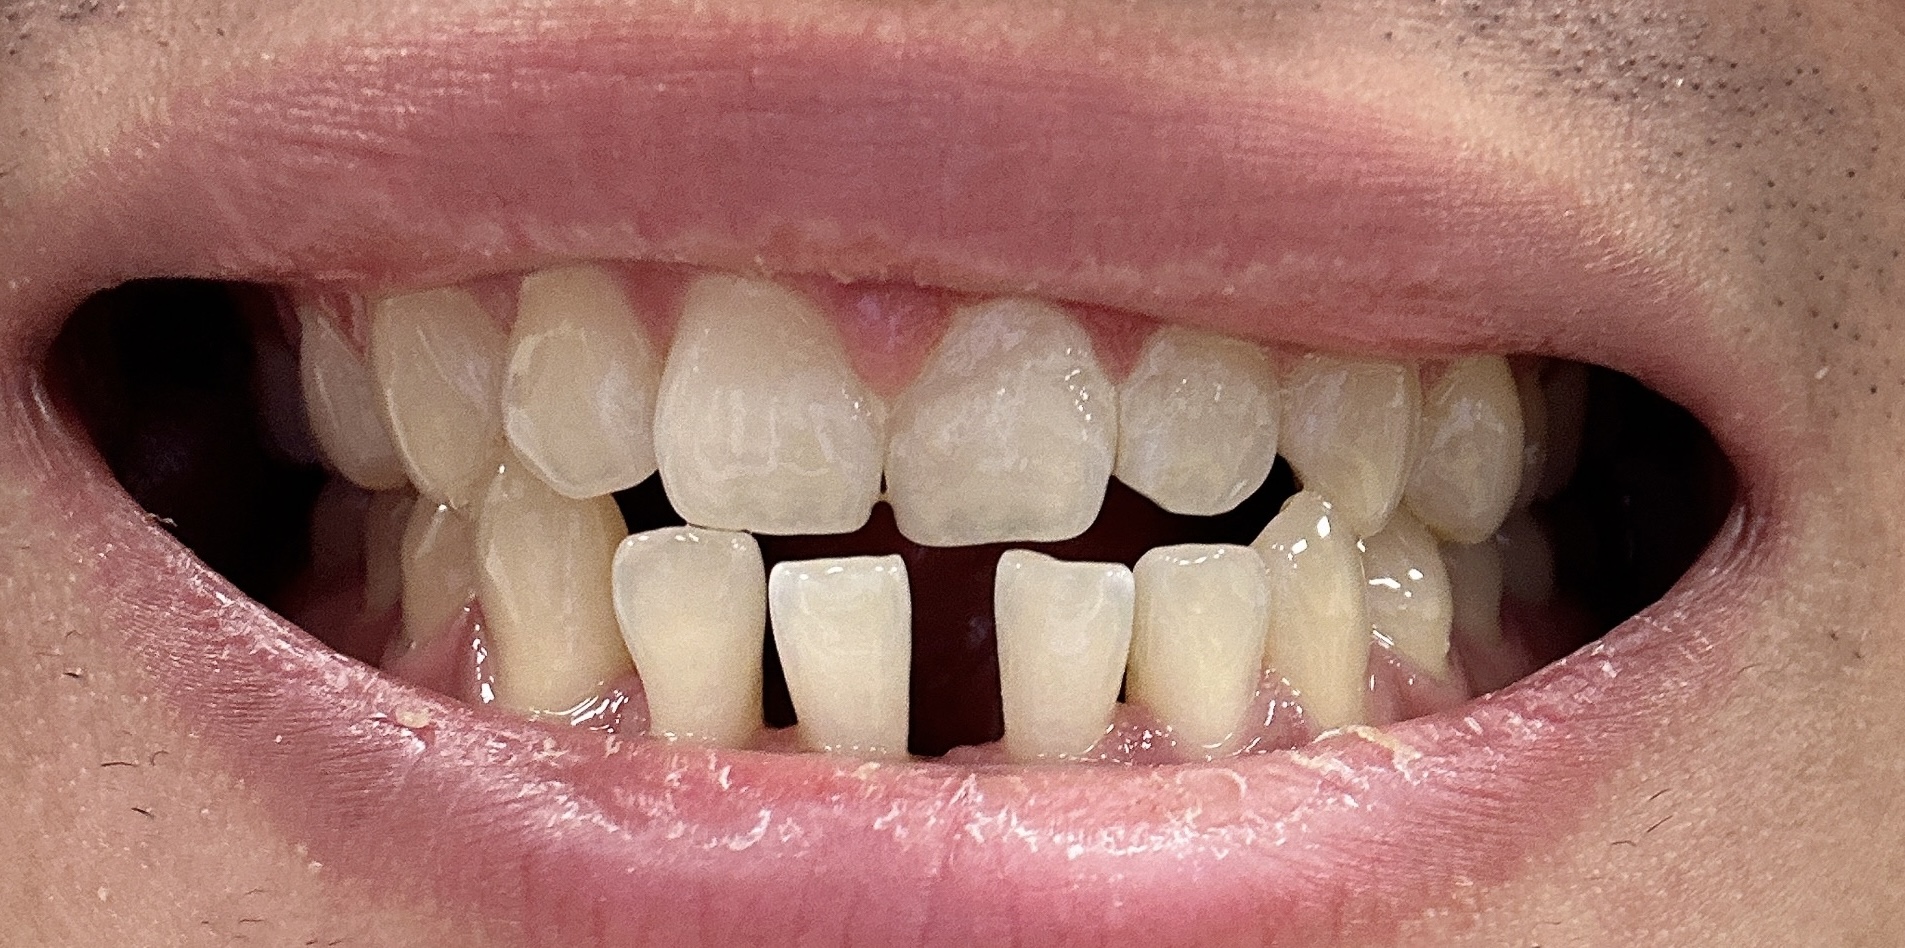

우선 교정을 시작하기 전의 모습이에요. 앞니가 많이 벌어진 상태로 점점 조금씩 돌아가고 있는 모습이 정말 보기 싫었는데요. 사실 거울을 보면서도 크게 못 느꼈던게 사실이었기 때문에 아무 생각을 안하고 있었는데, 확실히 교정을 하고 나서 모습을 보니까 잘 한거 같아요.

9월 이전 교정 전 모습

확실히 교정기를 장착하기 전에 많이 벌어진 모습이 보여요. 특히 앞니는 조금씩 더 돌아가고 있어서 교정을 고민하던 중에 결정하게 된 이유기도 해요.